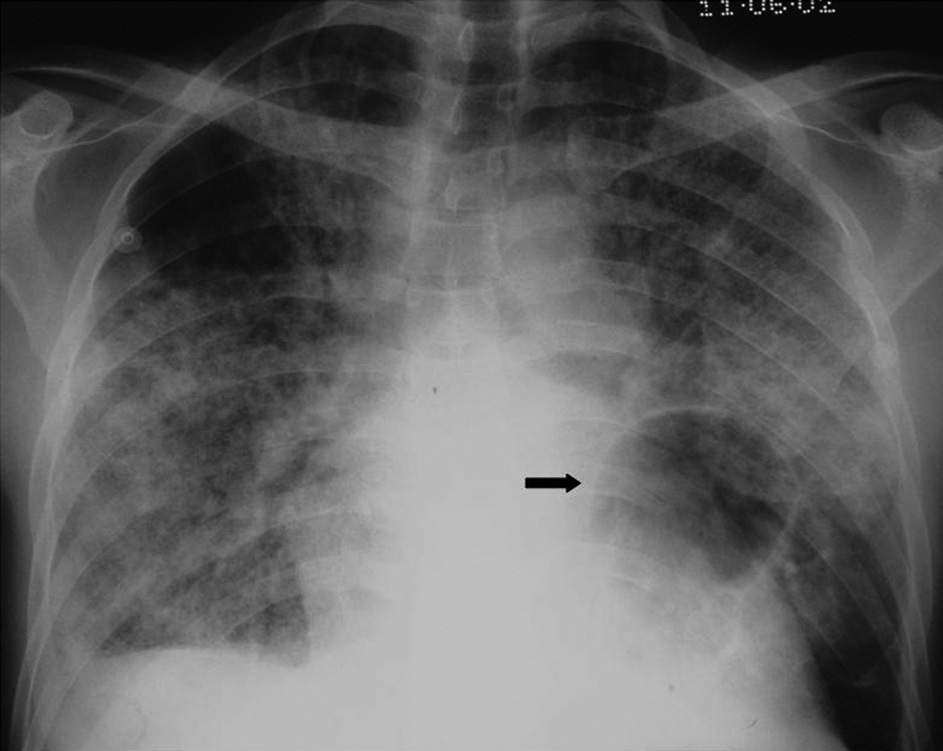

Фото: (2010). "Imaging lung manifestations of HIV/AIDS". Annals of Thoracic Medicine 5 (4): 201. DOI:10.4103/1817-1737.69106. ISSN 1817-1737, Carolyn M. Allen, Hamdan H. AL-Jahdali, Klaus L. Irion, Sarah Al Ghanem, Alaa Gouda, and Ali Nawaz Khan, Creative Commons Attribution 4.0 International license.